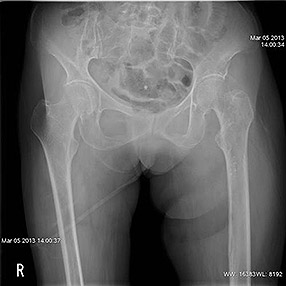

![]() 骨折部分がわかりにくいX線写真

高齢者の股関節は骨粗鬆等により骨折していても単純X線写真では判断しづらい場合があります。

そのような場合、今まではCT室に患者を移してCT検査を行う必要がありましたが、この撮影装置は

単純X線撮影を行った後そのままトモシンセシス(断層)撮影を行えます。

このようにX線撮影室で断層画像を作成できるようになり、救急患者さんの診断に大変役立っています。